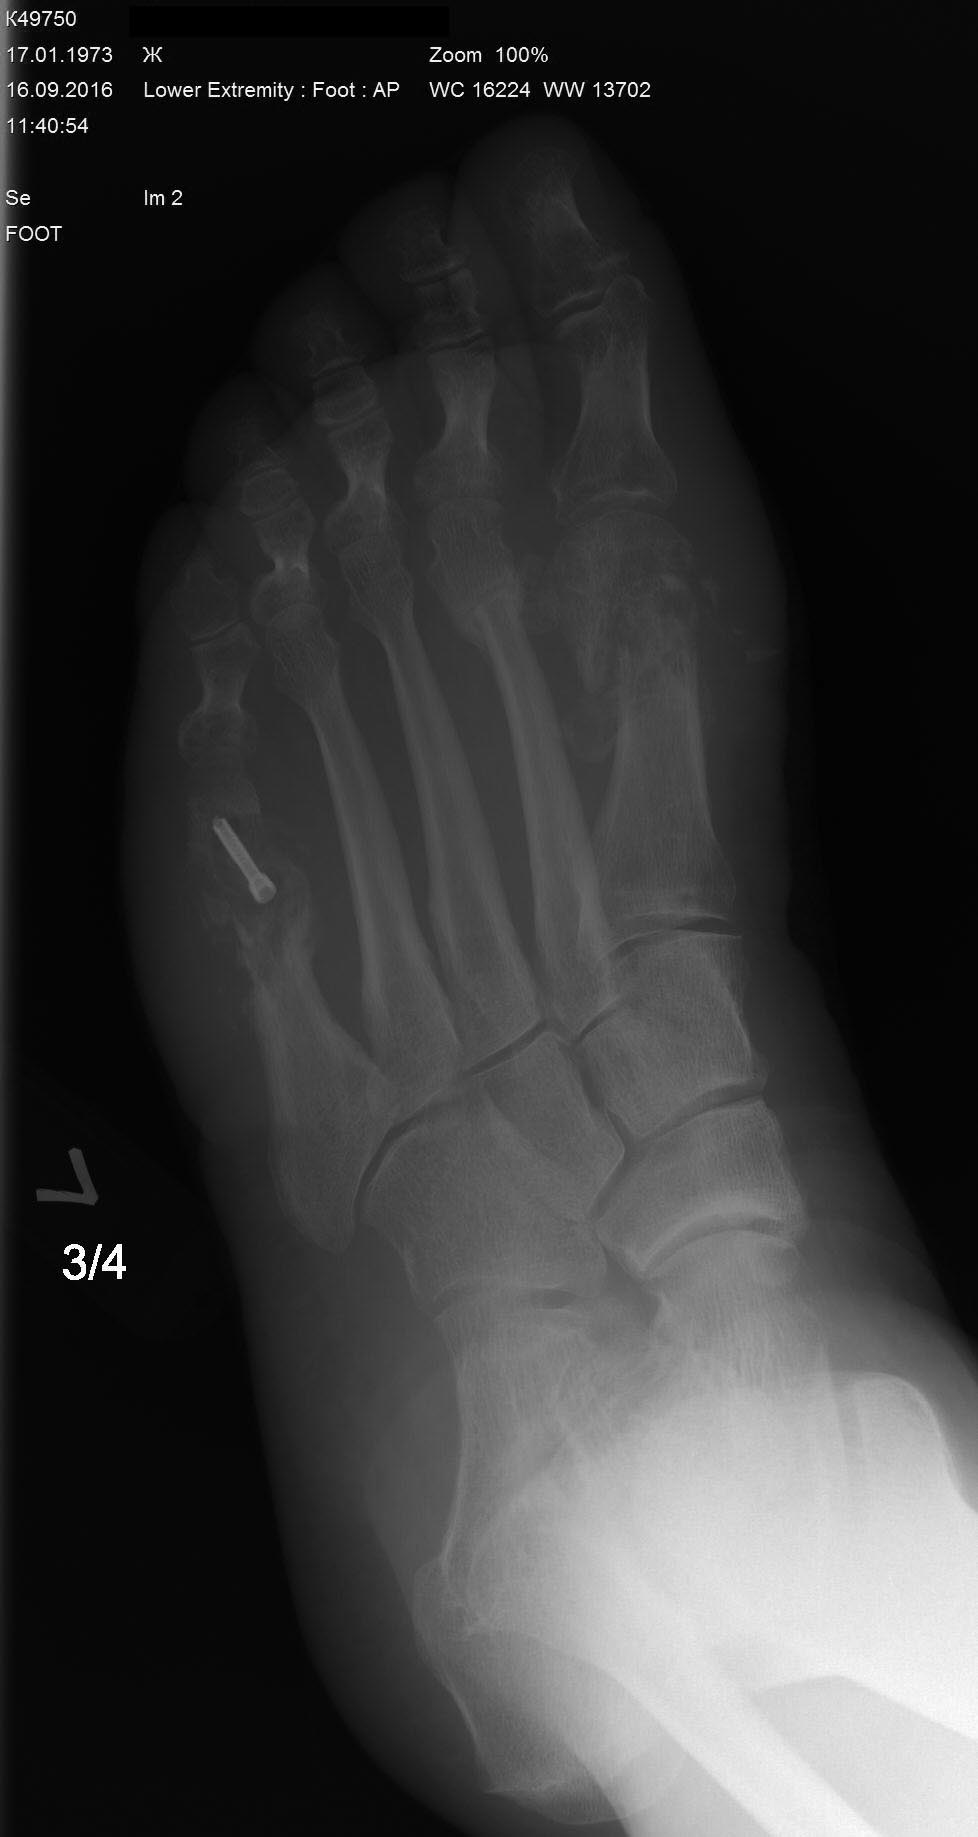

Пациентка 40 лет. Оперирована в июне 2016г- реконструктивная операция на 1-й плюсневой кости левой стопы по поводу вальгусной деформации 1-го пальца и на 5-й плюсневой по поводу деформации Тейлора. В стационаре после операции провела 5 дней, выписана в удовлетворительном состоянии со спокойными п/о ранами. Через 6 недель у пациентки в области п/о рубца в проекции 1-й плюсневой кости открывается свищ. Пациентка амбулаторно перевязывается.

Через 8 недель на Р-контроле выявляется миграция винта в 1-й плюсневой кости, который амбулаторно удален. Пациентка в этот момент жалуется только на отечность переднего отдела стопы и отделяемого свища. Лихорадку пациентка отрицает. В крови С-реактивный белок в норме, лейкоцитарная формула тоже в пределах нормы.

Через 10 недель пациентка приносит Р-контроль где имеются отчетливые признаки резорбции костной ткани в 1-й и 5-й плюсневых костях.

Не очень понятно, представленные снимки были сделаны до или после секвестрэктомии? Удален ли винт из пятой плюсневой? Когда и как (открыто или чрескожно) была выполнена остеотомия второй плюсневой кости? Был ли и где располагался свищ перед Вашей операцией? Ведь если при такой рентгенологической картине имеется всего один свищ в проекции первой плюсневой, нужно думать об обширном поражении тканей стопы. Что за отделяемое Вы обнаружили во время секвестрэктомии? Реальный гной? Были ли затеки, обнаружена ли общая полость между 1-й и 5-й плюсневыми? Через какие доступы была выполнена секвестрэктомия? Вовлечена ли, на Ваш взгляд, в процесс зона вмешательства на второй плюсневой? Действительно ли нужен аппарат внешней фиксации? Головка первой плюсневой не имеет никаких признаков консолидации? Без ответа на эти вопросы советовать сложно, описание не подробное и ситуация не понятна.